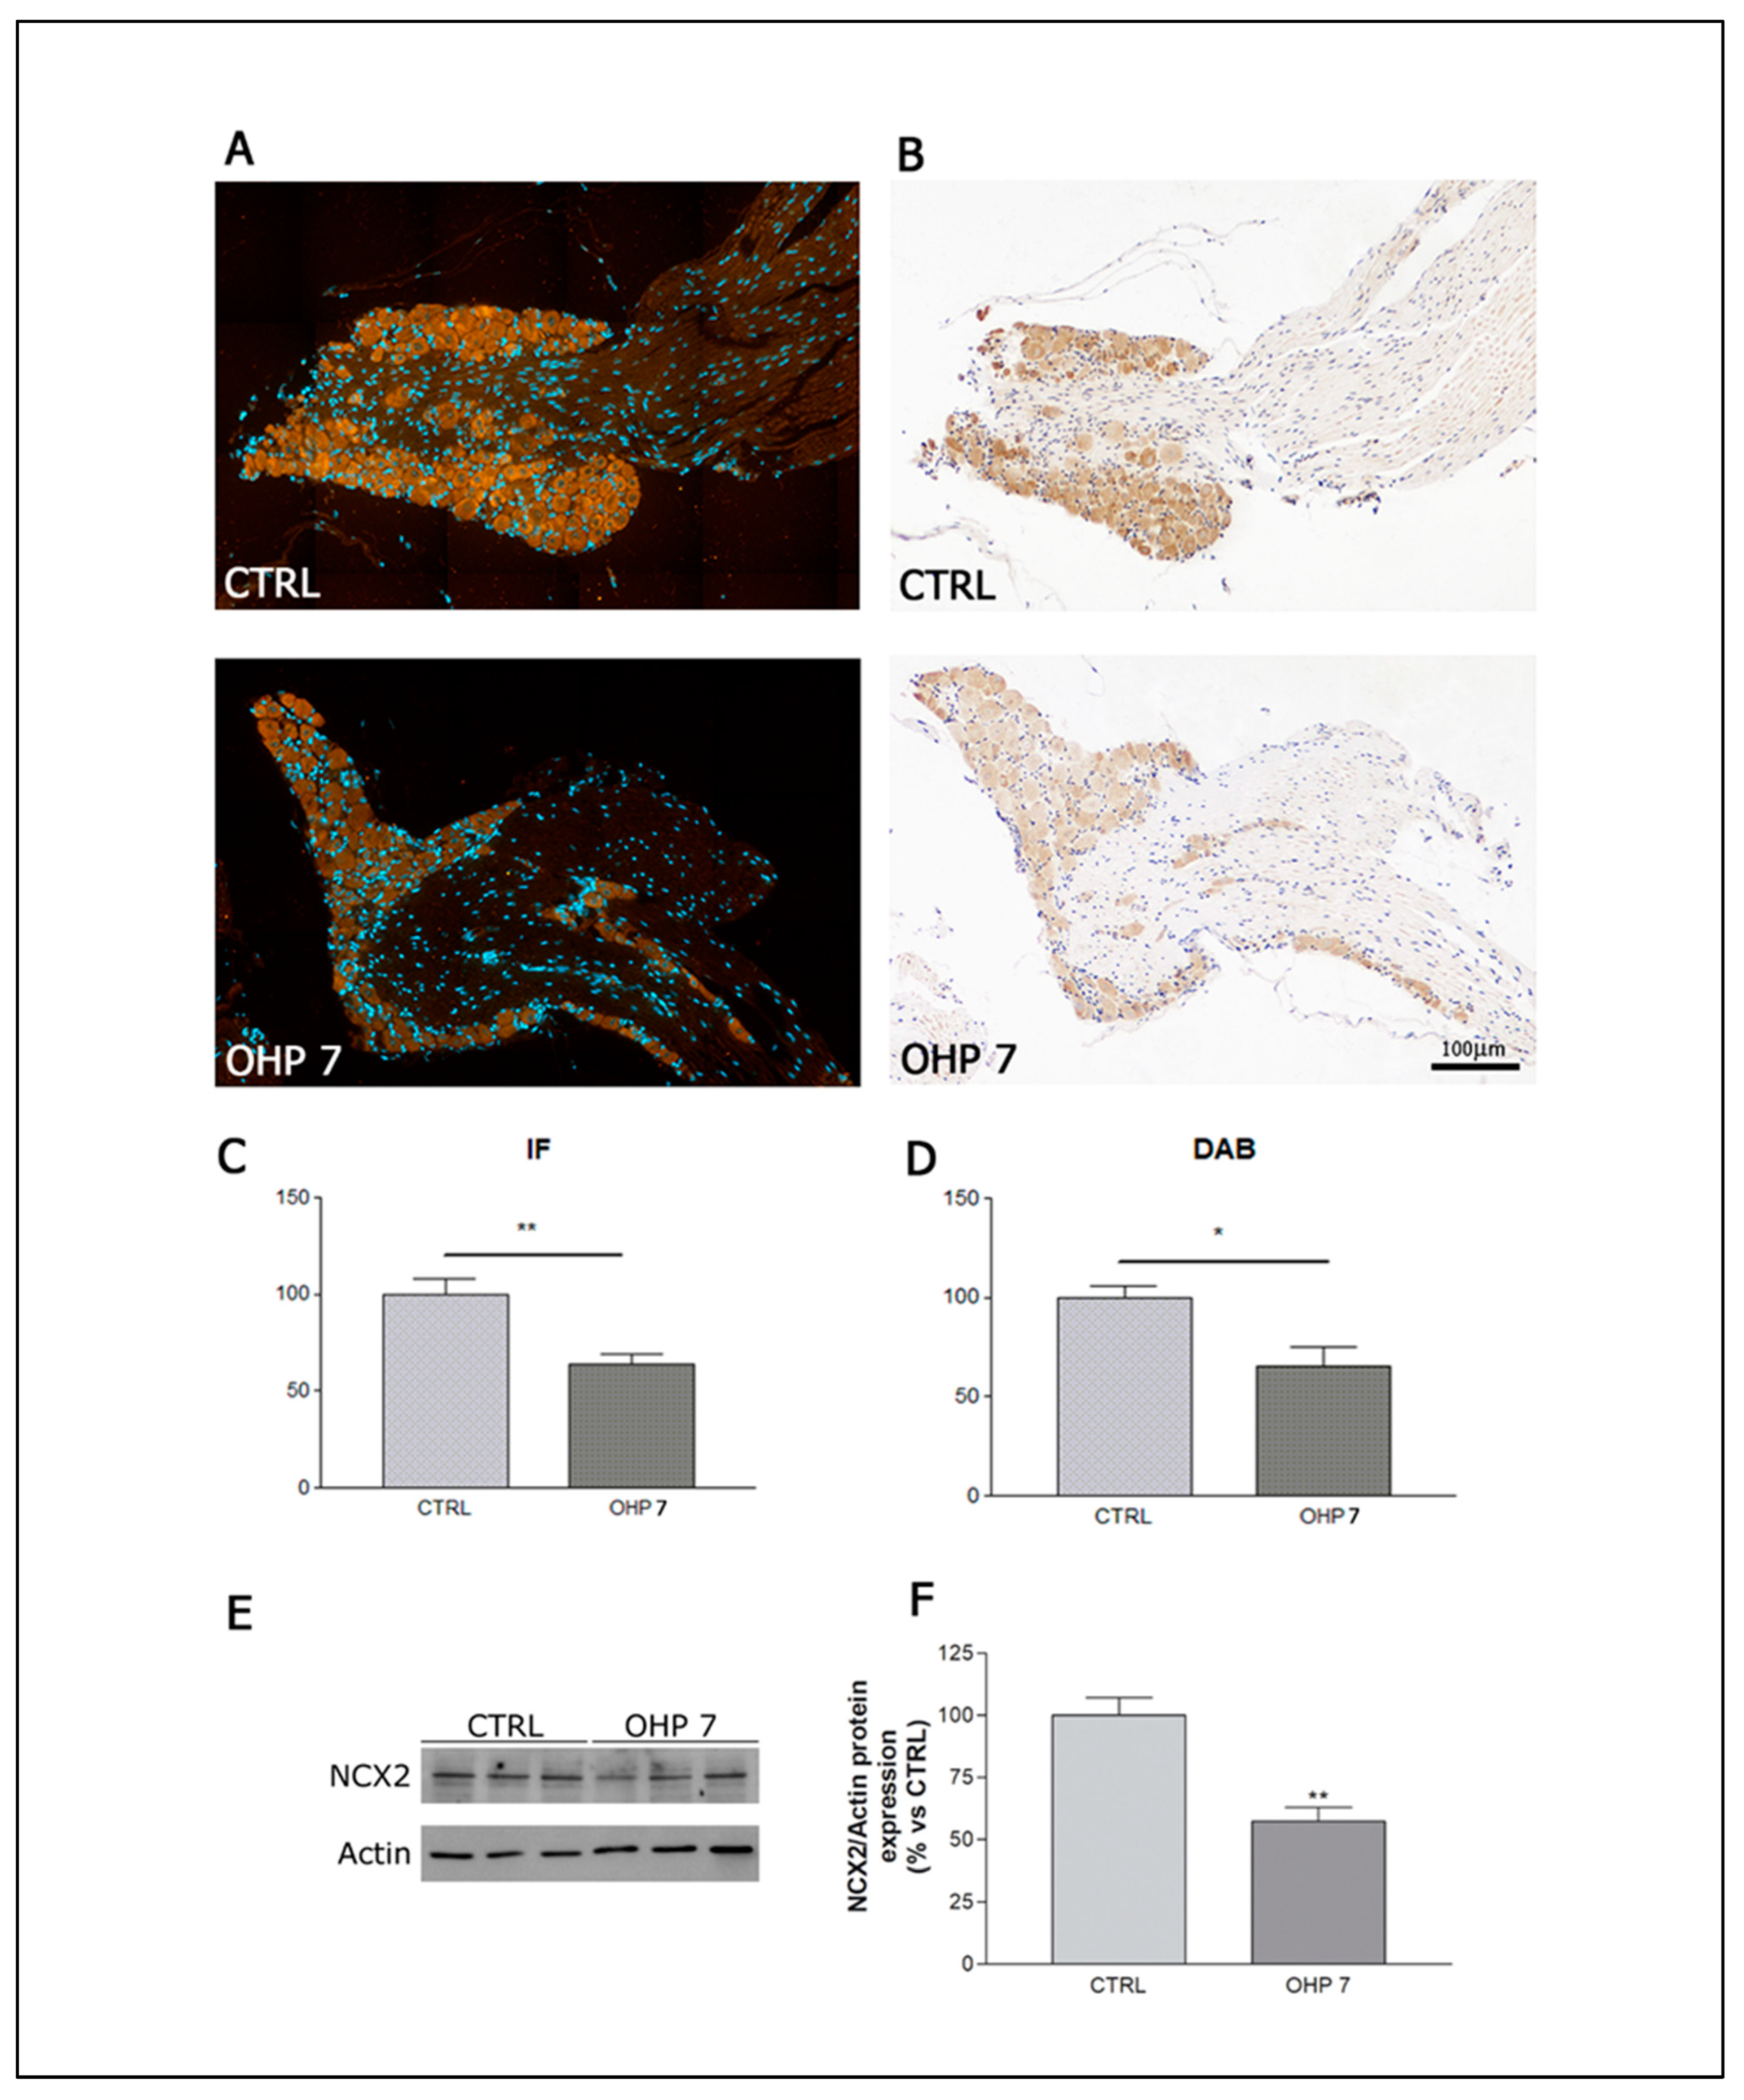

2.2.5. Immunohistochemistry (IHC), Immunofluorescence (IF), and Western Blotting (WB) for NCX2

4.2.7. Immunohistochemistry for NCX2

4.2.8. Immunofluorescence for NCX2

4.2.9. Western Blotting for NCX2